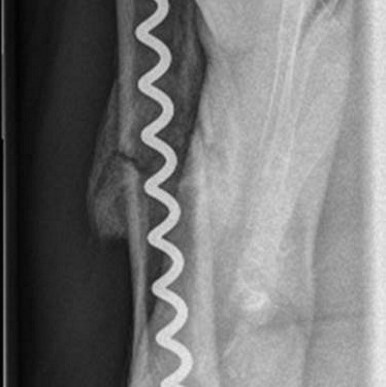

Dr. Senat Krasnici, Chefarzt der Klinik für Unfall- und Wiederherstellungschirurgie des Johanniter-Krankenhauses Genthin-Stendal, berichtet über seine Erfahrungen mit der Bonehelix als limitiertflexibler Markraumstabilisator.